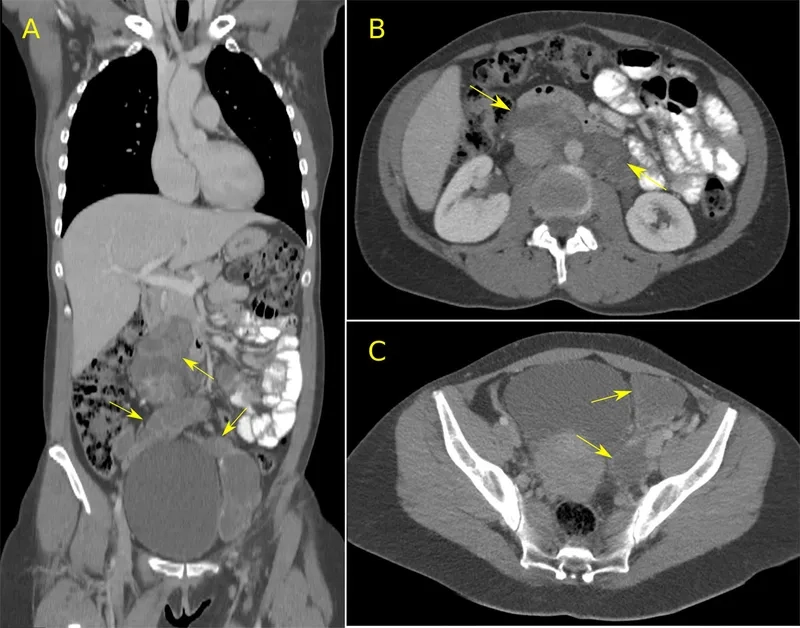

Image of the disease Lymphangioleiomyomatosis